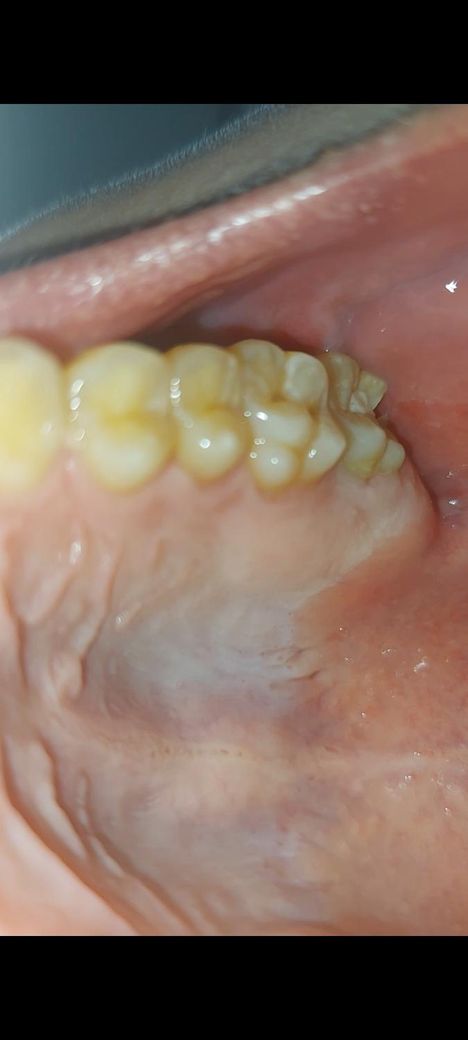

치아 깨짐 많이 심각한가요? (사진 o)

밥먹다가 윗니가 많이 뾰족해진 거 같아서 신경쓰여서 혀로 자꾸 만지작거리다가 부러지는 느낌과 함께 이빨 조각이 부러져나왔습니다. 휴대폰으로 찍어보니 저렇게 돼있더라고요.

치과를 가긴 할 건데 내일 아침에 당장 가야할 정도로 심각한가요? 아니면 금요일에 스케쥴 맞춰서 가도 괜찮을 정도인가요.

그리고 저 부분으로 음식을 씹거나 양치를 해도 괜찮은지도 궁금합니다.

사진상에서 가장 뒤쪽 치아가 깨진거 같습니다. 정확한건 엑스레이도 찍어보고 증상유무도 판단을 해보셔야될것같습니다.

사진으로 봤을 때는 맨 뒤에 있는 치아 뒤쪽으로 치아가 깨진 것으로 보입니다. 치아가 깨졌을 경우 충치가 원인이라면 충치를 치료해야 하며 치아를 씌워줘야 하는 경우도 발생할 수 있습니다

깨진 치아 부위로 음식을 씹지는 마시기 바랍니다. 시린 증상이 없다면 해당 부위 양치를 해도 크게 상관은 없습니다. 바로 치과를 가보세요

깨진 범위가 커 보이기는 하지만 증상이 없다면 금요일에 스케쥴 맞춰서 가도 괜찮을 정도입니다.